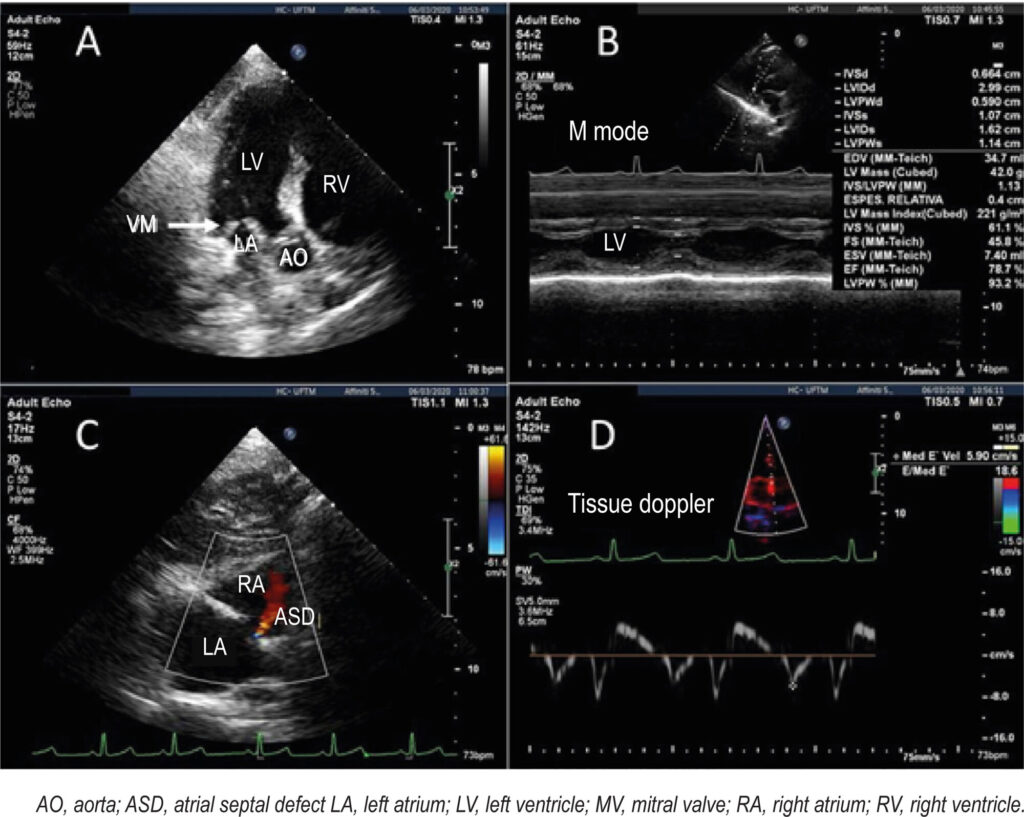

Mucopolysaccharidoses IV and VI: Aspects in Two-dimensional Speckle-tracking Strain Echocardiogram Imaging in a Case Series

Mucopolysaccharidosis (MPS) belongs to the group of lysosomal storage diseases associated with the partial or total deficiency of 11 different lysosomal hydrolases responsible for glycosaminoglycan (GAG) degradation. GAG accumulation may affect the valves, myocardium, and coronary vessels. The forms that accumulate dermatan sulfate (MPS I, II, VI, and VII) are associated with valvular thickening (L > R). MPS is one of the most common causes of mitral annulus thickening in children. Cardiac involvement also includes hypertrophy, tendinous cord shortening, and papillary muscle thickening. Echocardiography is an essential technique used to assess cardiac involvement in MPS. The study of myocardial strain using two-dimensional speckle-tracking echocardiography (2D-STE) provides a more sensitive evaluation of myocardial fiber strain that can reveal early and subclinical myocardial involvement regardless of left ventricular ejection fraction (LVEF) changes,.

This case series reviews relevant echocardiographic aspects of cardiac involvement complemented by 2D-STE in three patients with MPS during outpatient follow-up and taking enzyme replacement therapy (ERT).